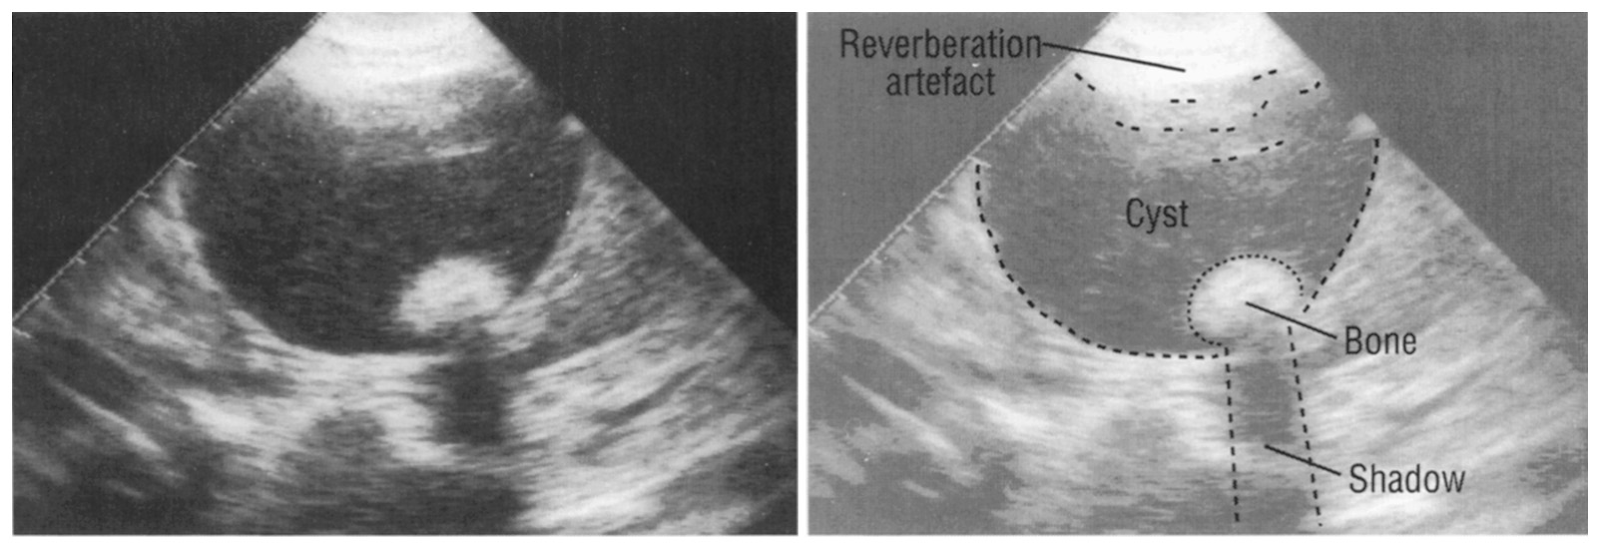

Тератома По Узи Фото

Тератома По Узи Фото 114 фотографий